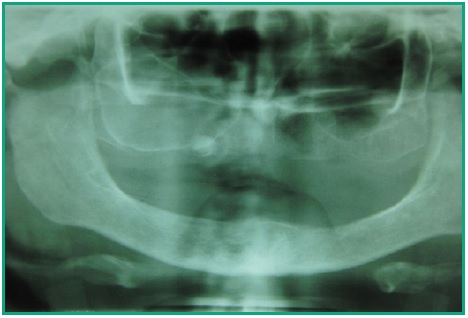

Se establece como diagnóstico clínico: quiste residual y como diagnóstico diferencial: quiste del desarrollo, tumor odontogénico y no odontogénico y mucocele. Se realizan radiografías periapicales, oclusal, teleradiografía de frente con incidencia de Waters y una ortopantomografía. Del conjunto se hace la siguiente lectura: lesión corticalizada con una extensión promedio de entre 25 mm. de alto y 35 mm. de largo, dividida la misma por un tabique. En la porción más posterior existe una ligera fenestración en el piso del seno maxilar. Se constata también un elemento radiopaco a la altura de la pieza dentaria 13 rodeado por un halo radiolúcido nítido (Fig. 3).